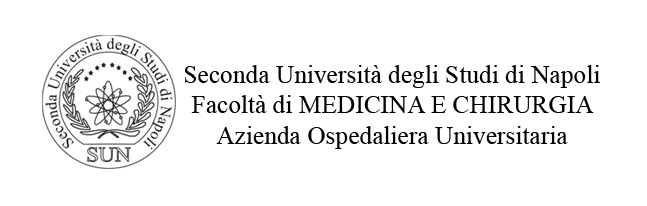

MICROAUTOFAGIA

I focolai di microautofagia si ritrovano frequentemente commisti a mitocondri disfunzionali e a reticolo- endoplasmatico in stato di stress.

Essi sono di piccole dimensioni, appaiono come vescicole, delimitate da una membrana a doppio strato, immerse nel citosol e

ricolme di materiale amorfo oppure di materiale amorfo commisto a frammenti filamentosi.

Fig.1  Fig.1a